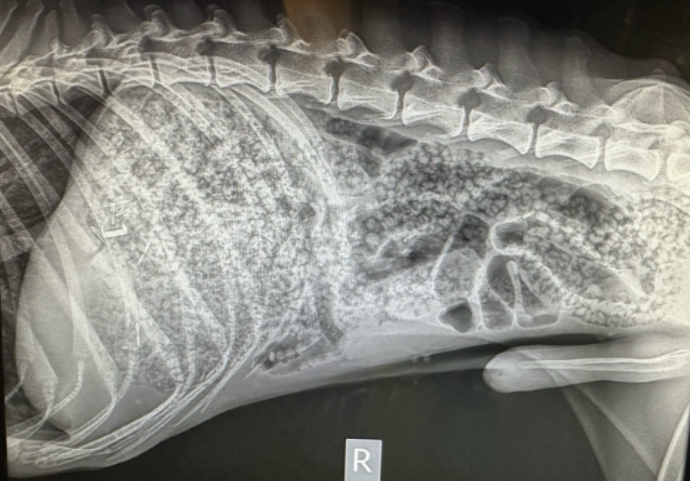

美國有獸醫助理近日在TikTok分享,指科羅拉多州一隻狗狗由主人帶來求診,沒料牠在診所中就地「大便」,但排出的並不是冀便,而是一粒又一粒,如雨水般落下的「彩虹珠珠」,看起來很有趣,但實際上很慘,可謂「狗狗心裡苦,但狗狗不說」。

原來該隻狗狗吞下了一大袋遇水會脹大的水晶珠,才導致牠「痾出彩虹」。據報狗狗本來是流浪狗,最近獲被收養,飽嘗過捱餓滋味的牠,胡思暮想的相信就是吃東西了,牠看到一袋水晶珠後,以為它是零食,便大口大口吃下,主人想阻止也來不及。

幸好據報狗狗接受手術後,已清除了吞下的七彩珠珠。有網民看罷片段稱,以為狗狗吃了「彩虹糖」,亦有人說以為是AI片段。